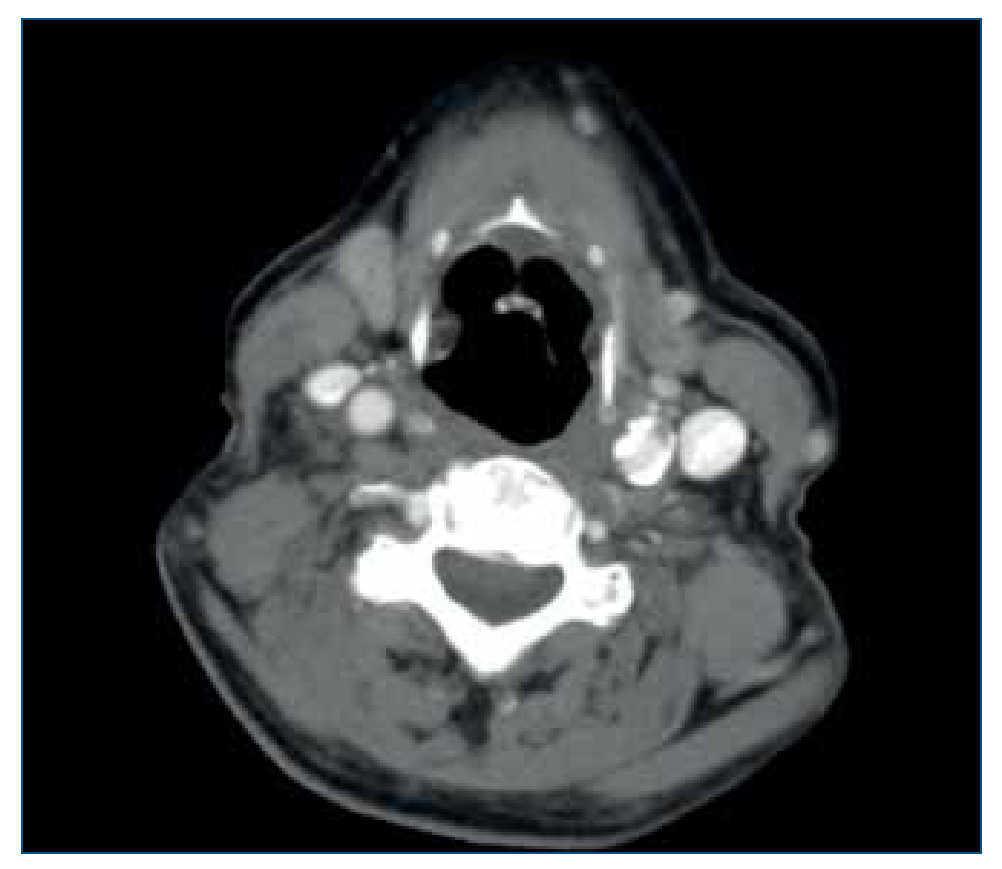

Presenta nódulo laterocervical derecho de crecimiento rápido (tres días), indoloro, sin signos inflamatorios ni repercusión sistémica. Ante la sospecha de un absceso cutáneo, se realiza incisión con drenaje sanguinolento, comenzando tratamiento antibiótico empírico. Valorado por Dermatología, establece el diagnóstico de sospecha de queratoacantoma. En la incisión quirúrgica se encuentra tumor muy friable, blanquecino, vascularizado e infiltrado hasta plano muscular superficial. La lesión es descrita histológicamente como proceso inflamatorio granulomatoso y supurativo con hiperplasia epidérmica pseudoepiteliomatosa, tractos de drenaje, áreas de necrosis, agregados epitelioides y células gigantes multinucleadas de tipo cuerpo extraño fagocitando fibras elastósicas, llegando a tejido muscular esquelético, compatible con pioderma blastomicoide. Los cultivos con y sin antibioterapia (vancomicina-ceftazidima) resultan negativos. Se realiza tomografía computarizada, observándose conglomerado adenopático laterocervical medio e inferior derecho con importante componente de partes blandas asociado, sugestivo de proceso neoformativo frente a proceso inflamatorio infeccioso (figura 1).

Figura 1.Tomografía computarizada inicial.